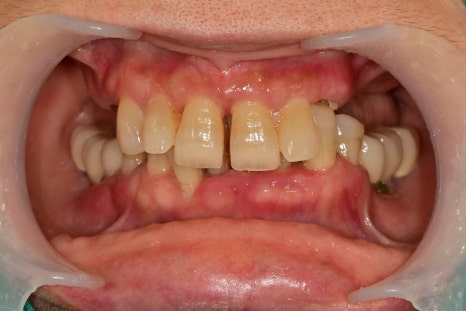

아래 앞니들은 치주염으로 인한 발치가 필요한 상황이며

위 앞니는 무너진 교합 때문에

앞으로 튀어나고 벌어져 있었습니다.

위 앞니를 보시면 무너진 교합을 회복시켜주고

자연치아가 회복할 시간을 주니

저절로 앞니도 이쁘게 제자리를 찾았습니다.

꽤나 긴 시간 동안 임시틀니를 사용하셨는데

이제 정상적인 저작을 하실 수 있다고 하셔서

너무 보람찬 순간이었습니다.^^